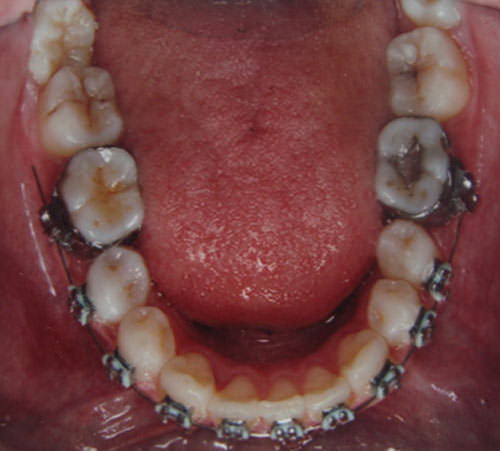

Se observa en las fotografías oclusales superiores e inferiores la forma de arco oval, presentando apiñamiento. En el arco superior los incisivos laterales se encuentran palatinizados los cuales están dentro del círculo azul y el canino izquierdo 23 fuera del arco. En el arco mandibular se observa el incisivo central 41 señalado en un cuadrado fuera del arco.

Fotografía oclusal inferior inicio